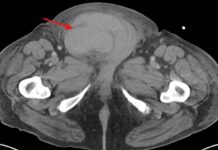

В ЦГКБ №3 Екатеринбурга зафиксирован необычный медицинский случай: у 63-летнего пациента диагностировали метастаз меланомы, хотя первичный очаг опухоли обнаружить не удалось. Мужчина обратился в клинику с жалобой на уплотнение в подмышечной области, которое при ультразвуковом исследовании оказалось увеличенным лимфоузлом размером 70/40 мм.

Врач ультразвуковой диагностики Жанна Краснопёрова пояснила, что для уточнения природы образования была проведена биопсия. «Гистологическое исследование подтвердило метастатический характер лимфоузла, — добавил онколог Андрей Лизунов. — Однако комплексное обследование с применением современных методов визуализации не выявило первичную опухоль».